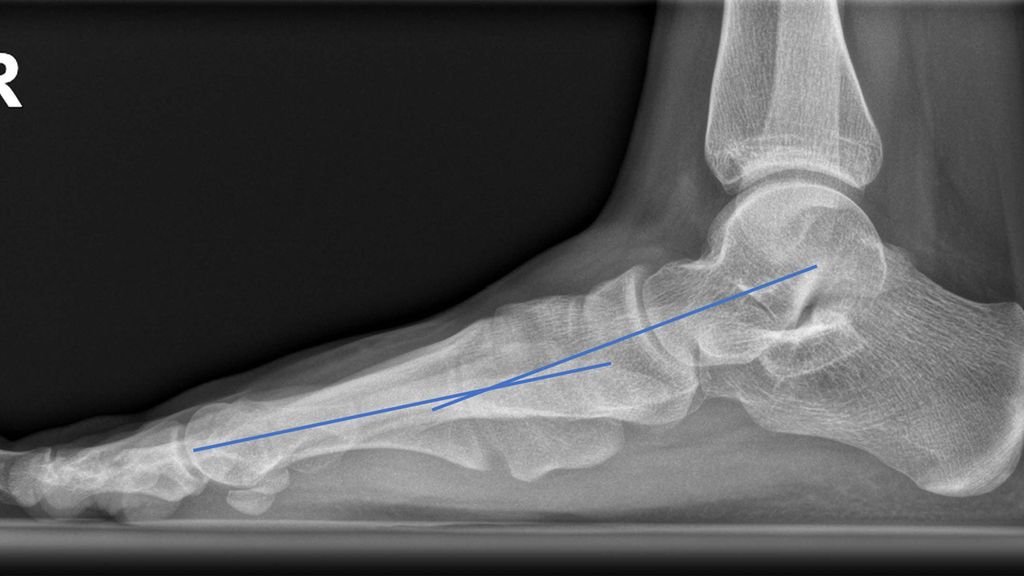

Abb. 1: Präoperativ: blaue Linie = Talus-MT1-Winkel; gebogene Linien: „talar head uncoverage“

Die d.p. Aufnahme zeigt das Ausmaß der Abduktion des Vorfußes, die talonaviculare Überdeckung („talar head uncoverage“, Abb. 1).3 Degenerative Veränderungen der einzelnen Gelenke werden beurteilt.

Auf der seitlichen Aufnahme sind die Abflachung des Längsgewölbes und die Lokalisation der gegebenenfalls vorliegenden Instabilität der medialen Säule zu erkennen (Talus-Metatarsale1-Winkel = „Meary’s angle“ 0°). Auch ein Metatarsus primus elevatus als Hinweis auf eine Supination des Vorfußes kann vorliegen (Abb. 2).